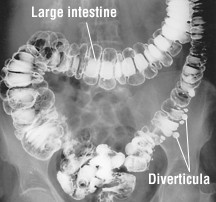

By the time most people reach the ripe age of 80, the smooth lining of their digestive tract is scattered with small, bulging pouches of tissue.

These sac-like protrusions along the digestive tract, called diverticula, are ‘weak spots‘ in the gut’s muscular wall. They are typically harmless, and most people never even know they are there.

While diverticula can develop in the large and small intestine, around 95 percent of patients in the Western world have diverticula in their sigmoid colon.

Diverticulosis can typically be diagnosed with a CT scan or colonoscopy.